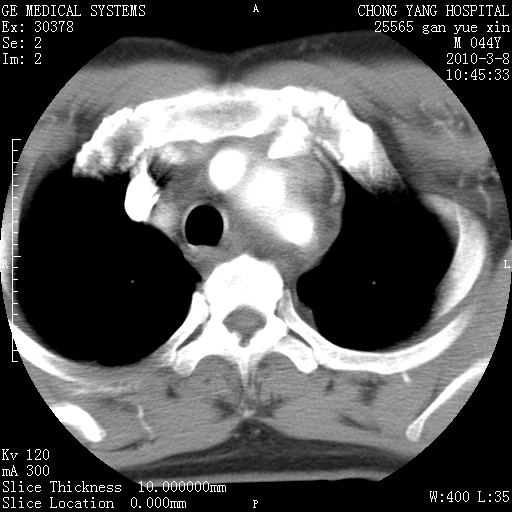

标题: CT24940:主动脉增强,典型病例。 [打印本页]

标题: CT24940:主动脉增强,典型病例。

夹层动脉瘤。

动脉夹层

夹层动脉瘤,典型

主动脉夹层。

动脉夹层的分型:

⒈debakey分型:根据主动脉夹层累及部位,分为三型:ⅰ型:原发破口位于升主动脉或主动脉弓部,夹层累及升主动脉、主动脉弓部、胸主动脉、腹主动脉大部或全部,少数可累及髂动脉。ⅱ型:原发破口位于升主动脉,夹层累及升主动脉,少数可累及部分主动脉弓。ⅲ型:原发破口位于左锁骨下动脉开口远端,根据夹层累及范围又分为ⅲa,ⅲb。ⅲa型:夹层累及胸主动脉。ⅲb型:夹层累及升主动脉、腹主动脉大部或全部。少数可累及髂动脉。

⒉stanford分型:a型:夹层累及升主动脉,无论远端范围如何。b型:夹层累及左锁骨下动脉开口以远的降主动脉。

夹层动脉瘤,少量胸水

夹层动脉瘤;左侧少量胸腔积液。

典型主动脉夹层。